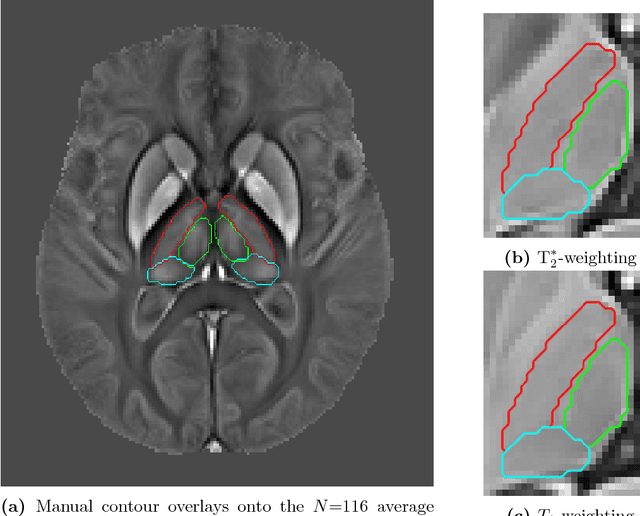

Abstract:Thalamic alterations are relevant to many neurological disorders including Alzheimer's disease, Parkinson's disease and multiple sclerosis. Routine interventions to improve symptom severity in movement disorders, for example, often consist of surgery or deep brain stimulation to diencephalic nuclei. Therefore, accurate delineation of grey matter thalamic subregions is of the upmost clinical importance. MRI is highly appropriate for structural segmentation as it provides different views of the anatomy from a single scanning session. Though with several contrasts potentially available, it is also of increasing importance to develop new image segmentation techniques that can operate multi-spectrally. We hereby propose a new segmentation method for use with multi-modality data, which we evaluated for automated segmentation of major thalamic subnuclear groups using T1-, T2*-weighted and quantitative susceptibility mapping (QSM) information. The proposed method consists of four steps: highly iterative image co-registration, manual segmentation on the average training-data template, supervised learning for pattern recognition, and a final convex optimisation step imposing further spatial constraints to refine the solution. This led to solutions in greater agreement with manual segmentation than the standard Morel atlas based approach. Furthermore, we show that the multi-contrast approach boosts segmentation performances. We then investigated whether prior knowledge using the training-template contours could further improve convex segmentation accuracy and robustness, which led to highly precise multi-contrast segmentations in single subjects. This approach can be extended to most 3D imaging data types and any region of interest discernible in single scans or multi-subject templates.